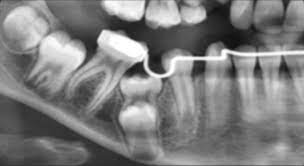

عکس گرافی دندان فک جوش

جراحی آنکیلوز که به عنوان آزادسازی آنکیلوز نیز شناخته می شود، برای رسیدگی به دندان جوش خورده و بازیابی عملکرد و زیبایی مناسب انجام می شود. روش جراحی دندان فک جوش شامل جداسازی دقیق دندان انکیلوز شده از استخوان اطراف است. در طول جراحی دندان فک جوش، جراح و متخصص جراحی فک وصورت برش هایی را در بافت لثه ایجاد می کند تا به ناحیه آسیب دیده دسترسی پیدا کند. سپس با استفاده از ابزار دقیق دندانپزشکی، دندان ذوب شده به آرامی از استخوان جدا می شود. در صورت نیاز، ممکن است از پیوند استخوان یا سایر مواد برای ارتقاء بهبودی مناسب و حمایت از ثبات دندان استفاده شود. سپس ناحیه جراحی برای تسهیل بهبودی بخیه می شود.